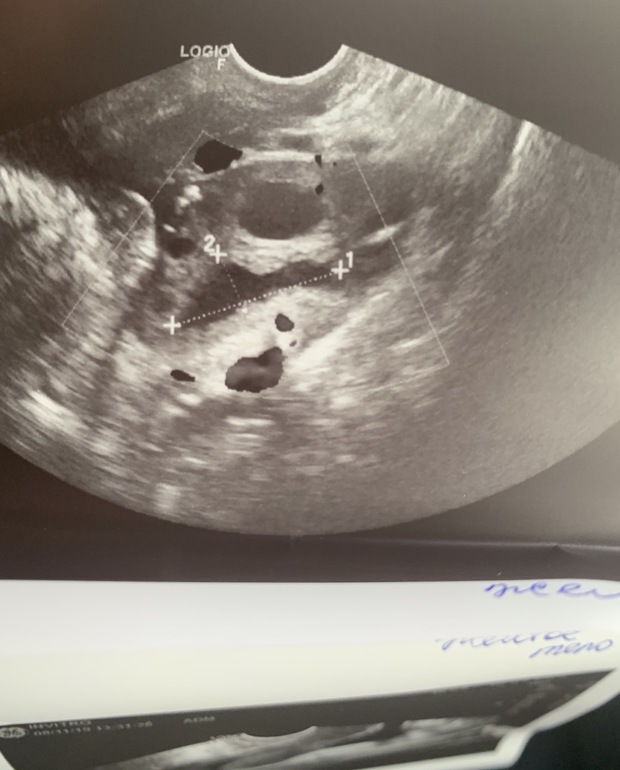

ЛОПНУЛИ, девочки!!!!! Фолликулы 26 и 27мм и сплющенное ЖТ

Первый цикл стимуляции клостилбегитом. На 10дц 2 доминантных фолликула в ЛЯ по 14мм, на 15 ДЦ Они же 26 и 27мм. Расстроилась. Тесты на овулю с 12дц пустые. Хотела вколоть укол хгч, но побоялась без врача и пошла качать пресс и ПАчиться. На работу одела самые маленькие джинсы, которые нашла и вечером на 16дц тестик первый раз мне улыбнулся))Сегодня 18дц на узи 2 желтых тела в ЛЯ 15 и 26мм и много жидкости в пм пространстве. Так много, что все распирает и тянет. Так что все бывает в этой жизни))такие значит у меня монстрики вырастают на клосте)))

(16дц: сделала на работе тест в 17:00, показался ярче, чем обычно, пришла домой где то в районе 20:30 сделала тест и он улыбнулся, но сомнения остались, не яркая какая то полоска была, вдруг ошибается, переделала ночью где то в 01:00 - уже ярче и тоже улыбался, а утром на 17дц где то в 10:00 на работе жирная вторая уже появилась)А вот одна из фоток сегодняшнего узи: два тела сказала узистка, одно сплющенное, длинное, 26мм, предположила, что оно лопнуло только что, и ещё не сформировалось, а второе круглое над ним, 15мм лопнуло вчера примерно.